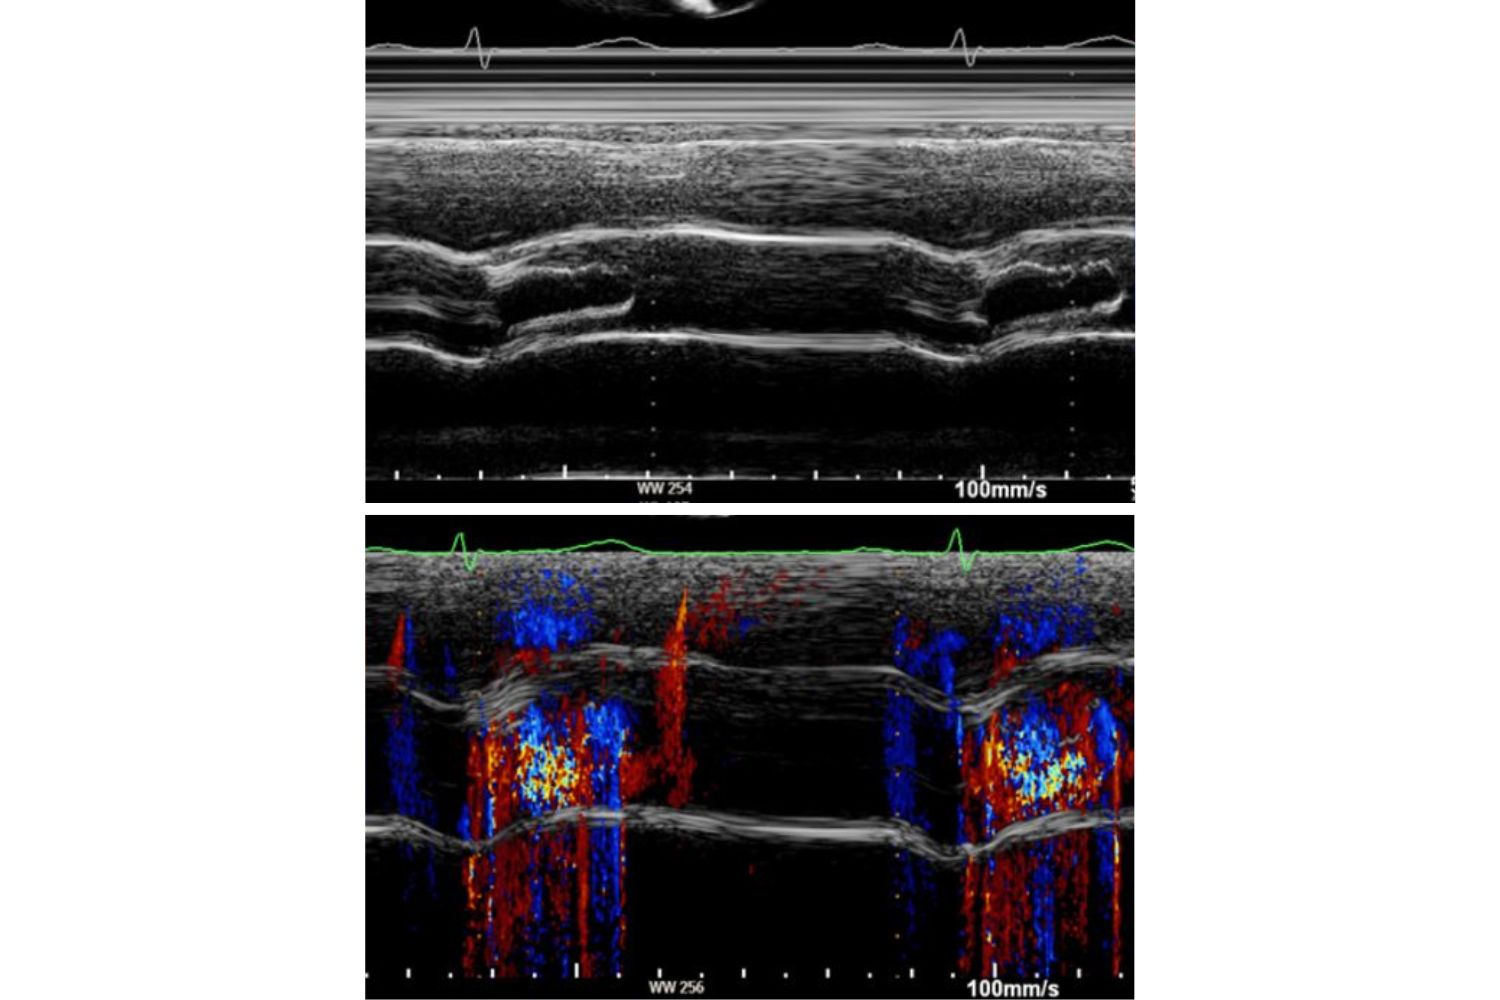

Image of the Week - 5 November 2025